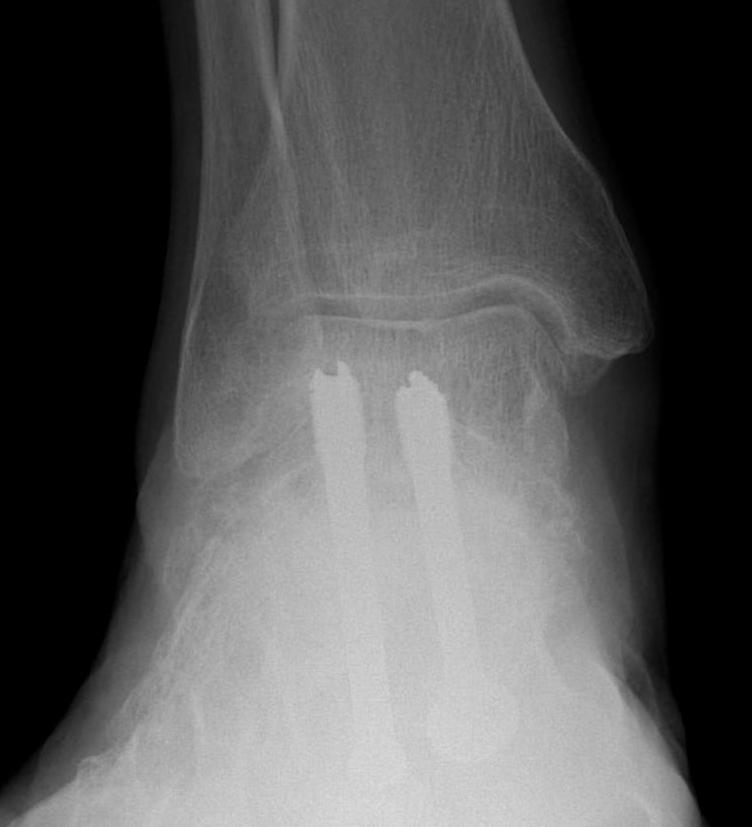

Fixation

- TJN screws

- CCJ screws +/- plate

- STJ screws